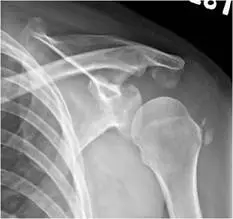

59 歲女性一個月前跌倒後出現左肩疼痛的症狀,影響睡眠,肩關節 X光檢查如附圖,最可能的診斷為何?

本題考的是肩關節 X 光影像判讀,需鑑別含鈣化沉積的病灶。59 歲女性跌倒後出現左肩疼痛一個月、影響睡眠,X 光顯示肩部特定位置有鈣化影像,最符合旋轉肌腱鈣化性肌腱炎(calcific tendinitis/calcified tendinosis)的表現。

影像二(另一角度或外旋位,AP view): 另一投影方向可見同樣的鈣化病灶,鈣化形態均勻,無骨小樑(trabeculae)結構,不具備真正骨化組織的特徵。鈣化位於肌腱走向區域,與肱骨大結節皮質之間仍可辨認有間隔,骨質本身完整無破壞,有助於與骨頭本身病灶(如轉移性骨癌、原發性骨腫瘤)區別。